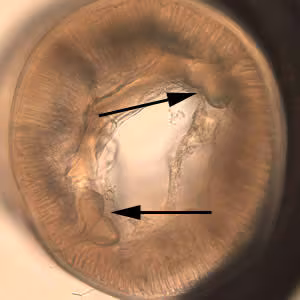

Anterior end of Pseudoterranova sp. The red arrow indicates the intestinal cecum.

Diagnosis can be made by gastroscopic examination during which the larvae are visualized and removed, or by histopathologic examination of tissue removed at biopsy or during surgery. Worms may be coughed up and brought in by patients.

Genus-level identification is not required for patient management but may be accomplished by examination of digestive structures and lateral chords. Examination of esophageal and intestinal morphology usually requires clearing in lactophenol.